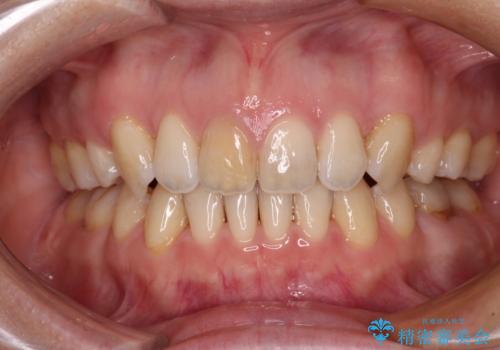

受け口傾向の咬み合わせ 前歯のデコボコをワイヤー矯正で素早く改善

この患者様もクロスバイトはあっという間に改善され、1年強で速やかに治療を終えることができました。